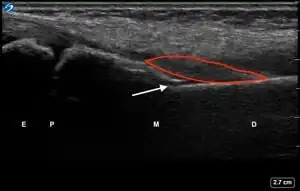

| 2 | Buckle (Torus) Fracture | "Bent" | ![]() Ultrasound dorsal view of buckle fracture of radius (shown by arrow). E = epiphysis; P = physis; M = metaphysis; D = diaphysis. | ||